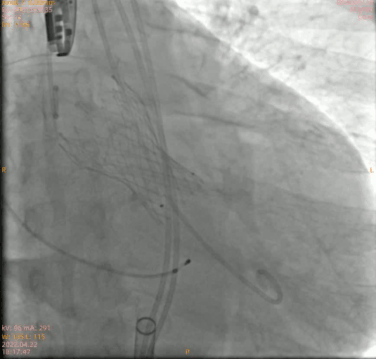

最终形态

术后即刻跨瓣压差测得小于 10 mmHg,手术结果理想。